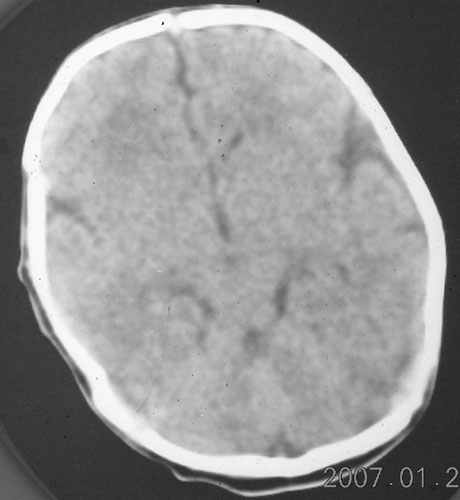

以下是引用rjg199343在2007-1-24 23:08:00的发言:[br]纵裂池、小脑幕、双侧脑室内高密度影,符合脑室、蛛网膜下腔出血。

以下是引用jiangjing在2007-1-24 23:31:00的发言:[br]纵裂池、小脑幕、双侧脑室内高密度影,符合脑室、蛛网膜下腔出血